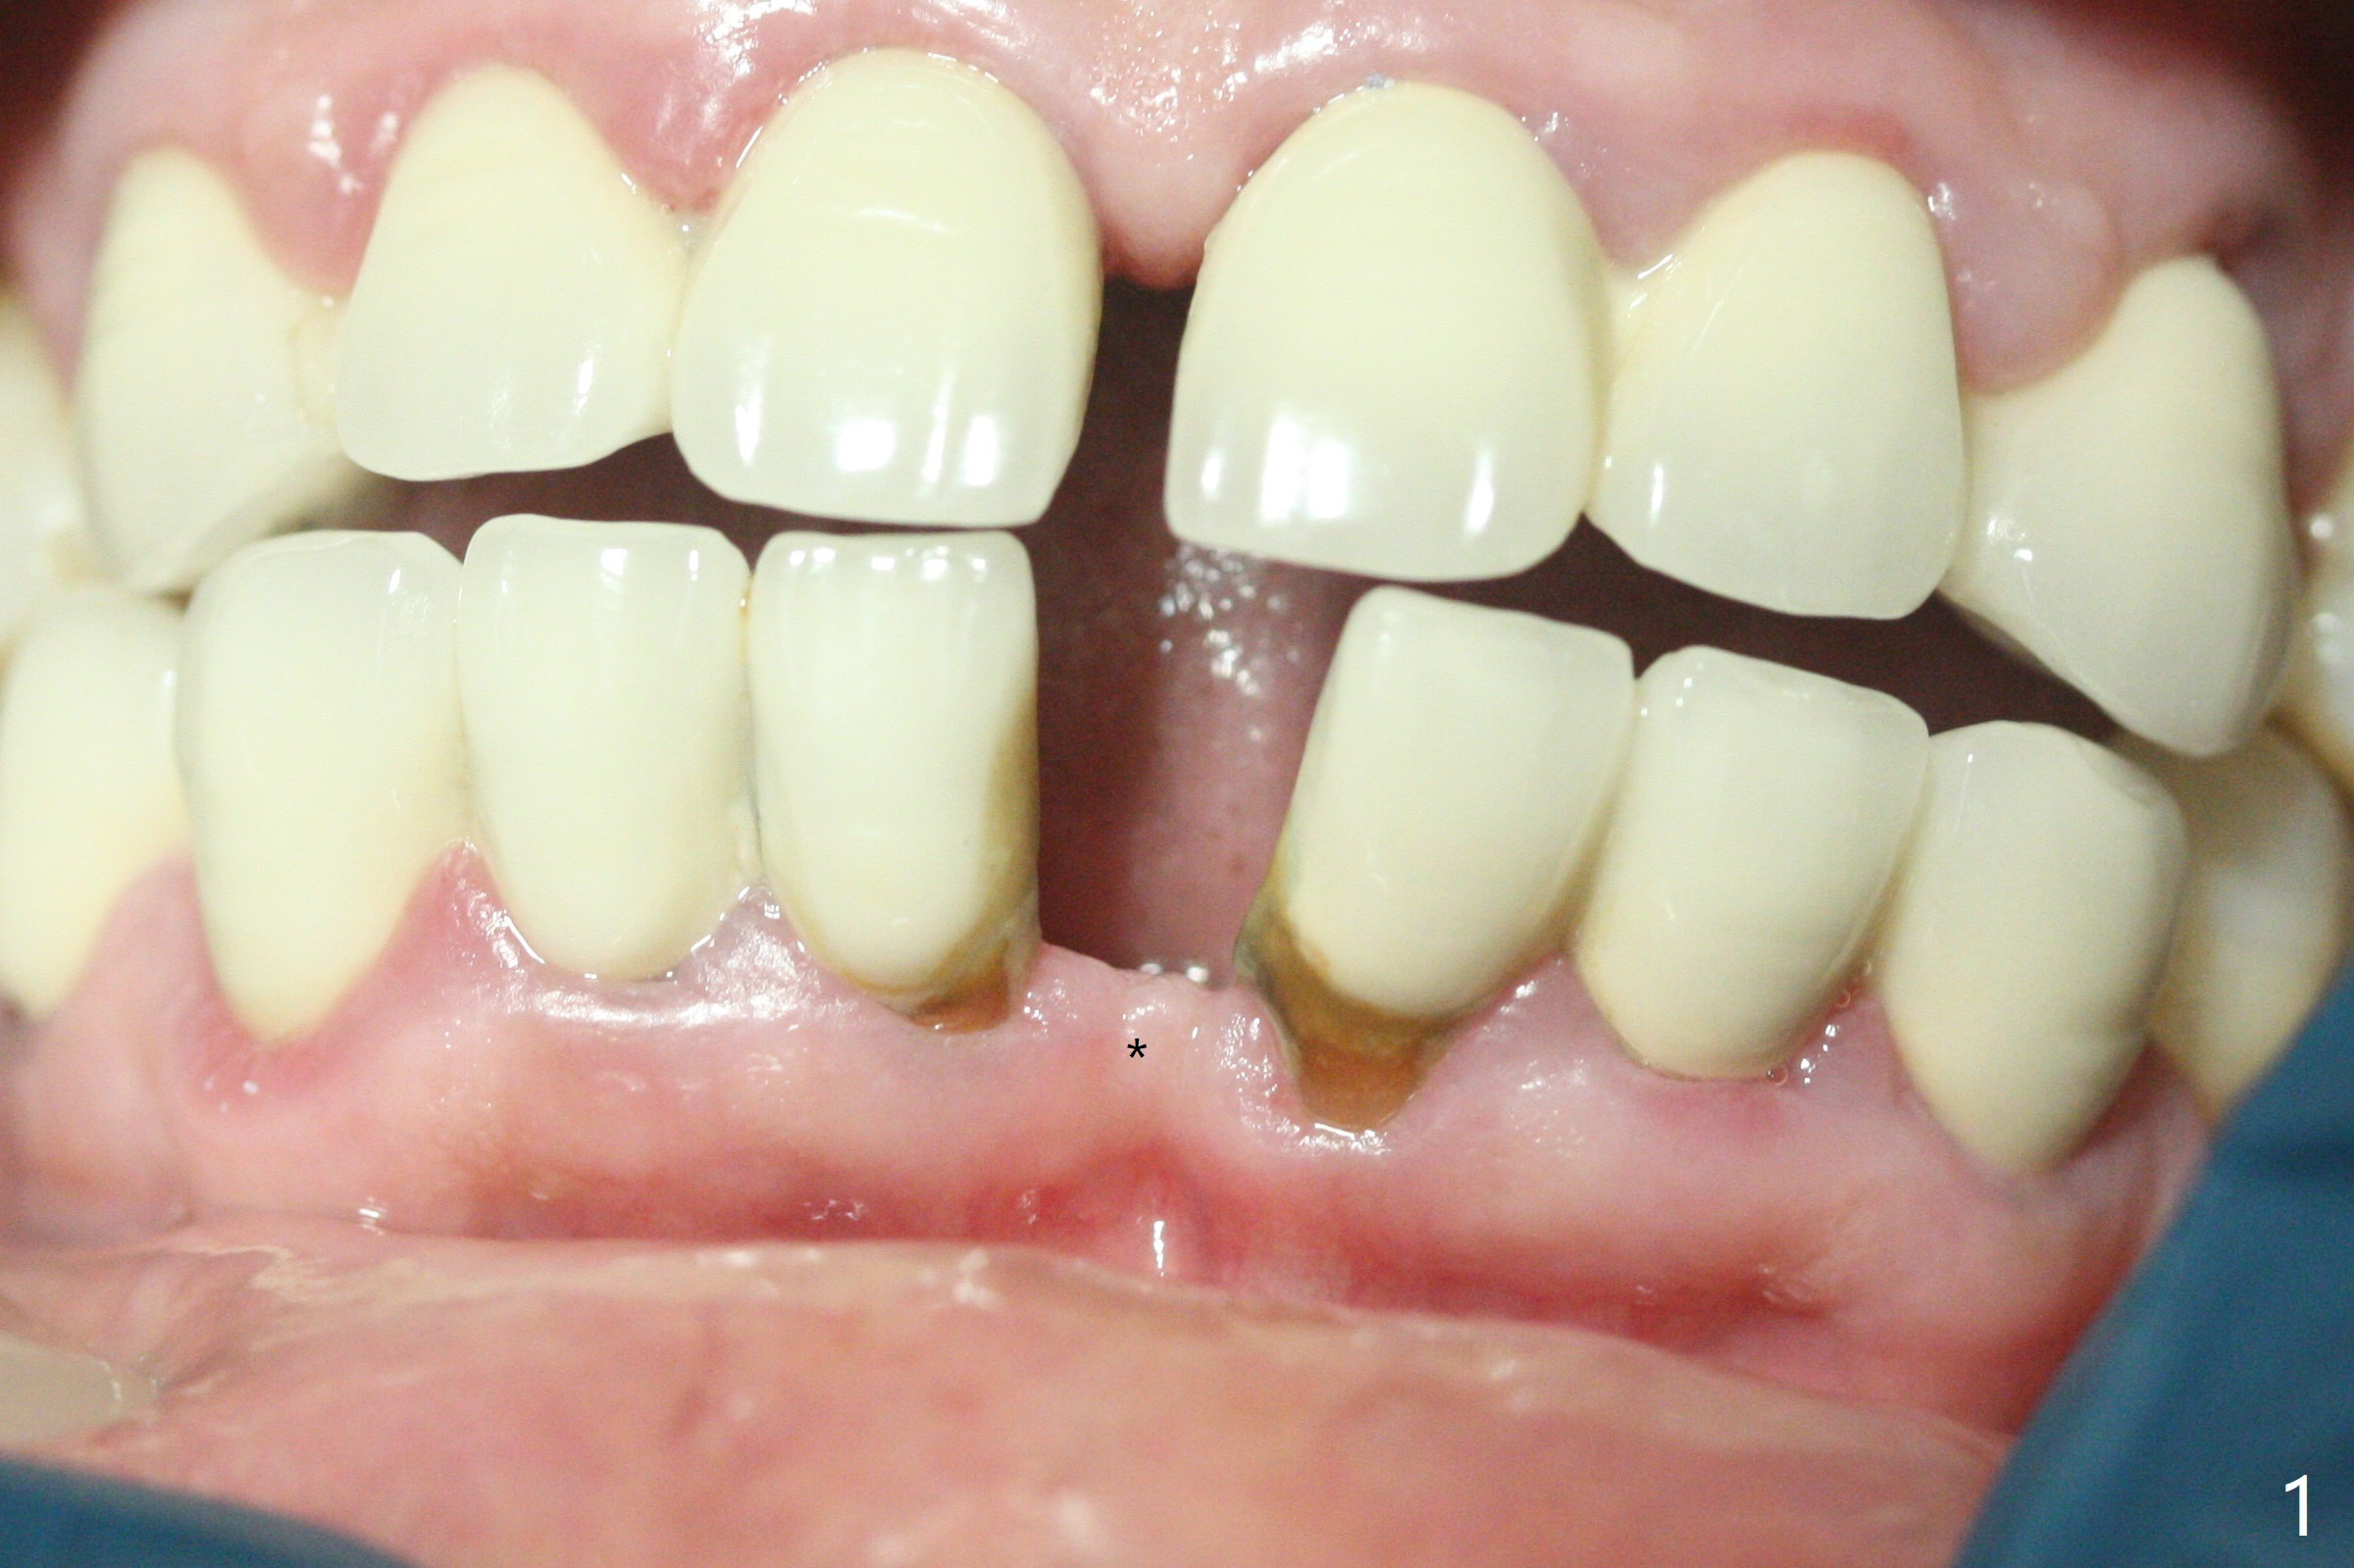

种植前与66岁女病人再次讨论下前牙正中种植可能产生不对称问题,她好像不在乎。术前检查显示下前牙正中间隙偏左(图一),处理似乎容易,但是牙槽嵴相当狭窄(图一 *,二 箭头)。牙槽嵴切除后(大约3 毫米宽(颊舌侧)),初期钻洞似乎偏移右边(图三),矫正后(图四),植入2乘10(4)毫米连体植体(图五,比预计小,因为骨质薄),放置骨粉(图五,六 *)和膜,缝合,制作即刻修复物(图七 T),病人满意,牙槽骨饱满了。术后一个多月临时牙冠取出修正,伤口愈合,由于植骨颊侧没有凹陷(图八),而舌侧隆起(图九:*,与图二术前对比)。其实病人不小心吃牛肉时损伤植体,疼痛几天。尽管最近吃饭时植牙又受伤,但是没有松动,也没有骨质吸收,就是局部结石多(图十,术后四个月)。正式牙冠术后4.5个月粘固(图十一)。